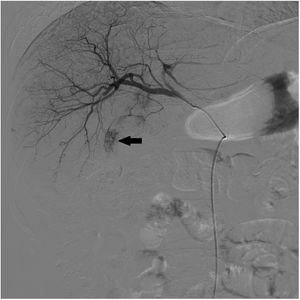

Presentamos el caso de un varón de 63 años con cirrosis hepática mixta (alcohólica y por virus de la hepatitis C) y diagnóstico de hepatocarcinoma de 14mm en segmento III y de 40mm en el segmento VI. Se realizó quimioembolización transarterial (QETA) de hepatocarcinoma mediante cateterización supraselectiva de las arterias nutricias de los nódulos tumorales y se embolizaron con doxorrubicina (DC-Beads 100-300 μ y 300-500μ) (fig. 1). Tras el procedimiento, apareció clínica compatible con retención urinaria, parestesias y paresia en ambos miembros inferiores con imposibilidad para deambular. En la resonancia magnética dorsolumbar urgente por sospecha de isquemia medular tras QETA se observó incremento de señal de la porción distal del cordón y del cono medular con moderada restricción en la secuencia de difusión (figs. 2-4), en posible relación con lesión isquémica aguda a nivel de T11, que la confirmó. Tras la rehabilitación, fue dado de alta con deambulación conservada.

La QETA tiene su base en la vascularización casi exclusivamente arterial que tiene el hepatocarcinoma1. En nuestro paciente es posible que el cuadro clínico presentado se explique por la existencia de una arteria nutricia del tumor como colateral de una de las arterias espinales que irrigan a la médula, pasando así el material quimioterápico a la médula espinal y provocando inusual isquemia medular aguda transitoria.